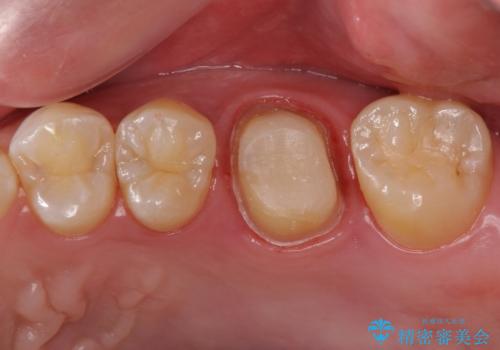

不適合な被せ物 ジルコニアクラウンでの再治療

- 検査の結果被せ物の不適合が見つかった患者様です。

ご妊娠中で安定期に治療を終わらせたいとのご希望があったため、大掛かりな外科処置は避けた治療方針で進めていきます。

被せ物を除去し、根管治療を進めた後に新しい被せ物を装着していきます。